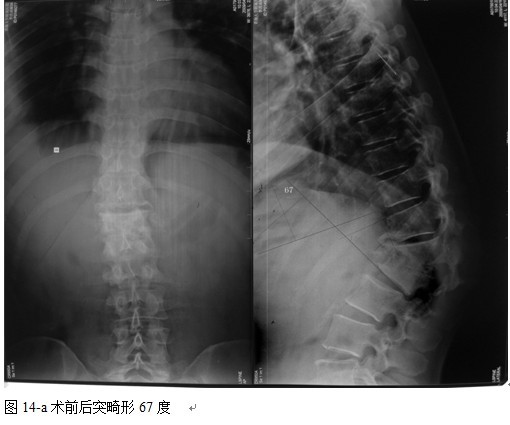

本组46例中男28 例,女18 例。年龄17~67岁,病程6 个月~7年,平均11.3 个月。本组患者均为 L1~S1腰段结核。病灶累及2 个椎体31例(L1-2 6例, L2-3 8例,L3-4 10例,L4-5 5例,L5-S1 2例),3 个或3 个以上椎体15例。合并腰大肌脓肿23列,所有患者均有腰背部疼痛,活动受限,双下肢感觉麻木19例,会阴部感觉减退12例,双下肢肌力减弱12例,腱反射减弱12例,术前后凸角(Cobb 角) <30°者12例, 30°~60°者28 例, >60°者6 例,Cobb角平均32.3°4例患者是二次手术。术前均行X线片、CT或者MRI检查。术后病理检查确诊为脊柱结核。

本组手术用时间3~4h , 平均3.5h 。术中出血300~500ml , 平均约350ml 。术后症状完全缓解,无神经功能障碍加重等并发症,1例营养差的老年患者伤口出现窦道,1例因肝功能差,术后未口服抗痨药,伤口出现窦道,经换药后二期愈合,其余病例伤口均一期愈合。马尾神经受损的患者术后基本恢复正常。术后一周后凸角平均 5.4°后凸畸形平均矫正90%以上, 最终后凸角平均8.3°,后凸角度平均丢失4.2°。随访3个月有87%(40/46)有骨痂形成,6个月91.3%(42/46)明显骨性愈合(见图),其余4例9-12个月内愈合,随访时间3-32个月,平均11个月,46例患者中2例在术后2个月和3个月时背部形成脓肿,换药后治愈。2例出院1月后并发结核性脑膜炎,治疗后好转。1例因椎弓根钉偏外,刺激神经根,5个月后从侧方脱出,疼痛加重,因前后路植骨完全愈合,取出后症状完全缓解。

中国学者金大地[22]等采用一期前路病灶清除植骨前路钢板固定治疗腰椎结核,平均18°的后凸畸形得以矫正,Mukhtar[23] AM等采用前路病灶清除植骨分期或同期后路固定治疗腰椎结核22例,术后后凸畸形矫正度数平均为27°。从我们的随访结果看,术后后凸畸形平均矫正度数为26.9°,后凸畸形平均矫正90%以上, 6个月-49个月后随访,后凸角度平均丢失4.2°。本术式也适用于结核所引起的弹性差的后凸畸形,对于病灶纤维化或骨化的非弹性后凸畸形,后路固定后,先行前路病灶、纤维化或骨化切除、松解,逐步刮除病灶、逐步撑开,达到畸形矫正和植骨的目的。